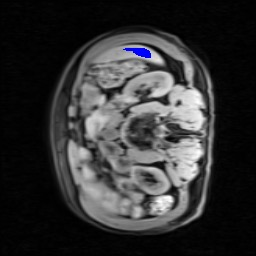

Transformers have made remarkable progress towards modeling long-range dependencies within the medical image analysis domain. However, current transformer-based models suffer from several disadvantages: (1) existing methods fail to capture the important features of the images due to the naive tokenization scheme; (2) the models suffer from information loss because they only consider single-scale feature representations; and (3) the segmentation label maps generated by the models are not accurate enough without considering rich semantic contexts and anatomical textures. In this work, we present CASTformer, a novel type of generative adversarial transformers, for 2D medical image segmentation. First, we take advantage of the pyramid structure to construct multi-scale representations and handle multi-scale variations. We then design a novel class-aware transformer module to better learn the discriminative regions of objects with semantic structures. Lastly, we utilize an adversarial training strategy that boosts segmentation accuracy and correspondingly allows a transformer-based discriminator to capture high-level semantically correlated contents and low-level anatomical features. Our experiments demonstrate that CASTformer dramatically outperforms previous state-of-the-art transformer-based approaches on three benchmarks, obtaining 2.54%-5.88% absolute improvements in Dice over previous models. Further qualitative experiments provide a more detailed picture of the model's inner workings, shed light on the challenges in improved transparency, and demonstrate that transfer learning can greatly improve performance and reduce the size of medical image datasets in training, making CASTformer a strong starting point for downstream medical image analysis tasks.